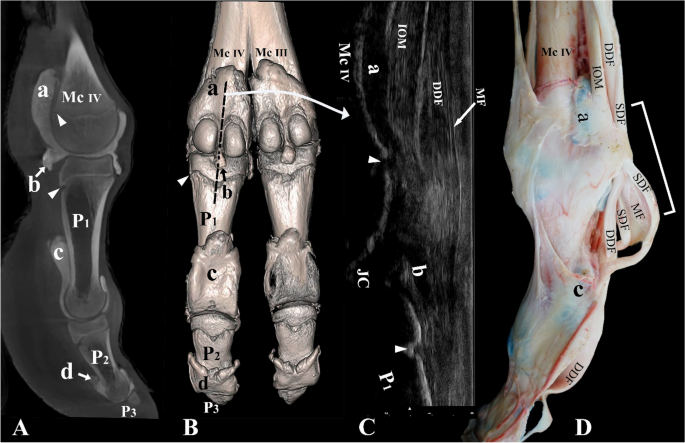

Dorsal view of the left distal forelimb. (A) Bones, (B) casting, (C) dissection, and (D) arthrocentesis approaches on an intact specimen. Mc metacarpal bone, Mc III distal end of metacarpal bone III, Mc IV distal end of metacarpal bone IV, P1 and P1′ proximal phalanx, P2 and P2′ middle phalanx, P3 and P3′ distal phalanx, a and a′ proximal dorsal recess of the metacarpophalangeal joint, b and b′ distal dorsal recess of the metacarpophalangeal joint, c and c′ proximal dorsal recess of the proximal interphalangeal joint, d and d’ distal axial recess of the proximal interphalangeal joint, e and e′ proximal dorsal recess of the distal interphalangeal joint, 1 medial tendon of the common digital extensor muscle, 2 lateral tendon of the common digital extensor muscle, 3 lateral digital extensor tendon, 4 continuation of the lateral tendon of the common digital extensor muscle, 5 proper extensor tendon of digit III, 6 proper extensor tendon of digit IV, 7 fat pad, DMp dorsal arthrocentesis approach to the metacarpophalangeal joint, DPI dorsal arthrocentesis approach to the proximal interphalangeal joint, DDI dorsal arthrocentesis approach to the distal interphalangeal joint. The black asterisks indicate the extensor process of the middle and distal phalanx.

The two metacarpophalangeal and two metatarsophalangeal joints are formed by the trochlea of metacarpal/metatarsal bone III and IV, the proximal articular surface of P1, and the palmar/plantar located proximal sesamoid bones (Figs. 1A, 2A, 4A). Each of these joints has an individual joint capsule, which means that the two joint cavities of the metacarpophalangeal and metatarsophalangeal joints are separated (Fig. 1B).

Dorsally, the metacarpophalangeal/metatarsophalangeal joint capsule forms a proximal recess that extends to the level of the epiphyseal line of the metacarpal/metatarsal bone (Fig. 1B). Another recess is formed by the capsule in a dorsodistal manner and extends to the level of the epiphyseal line of P1 (Fig. 1B). Palmar/plantar, the joint capsule forms a large proximal pouch that extends beyond the epiphyseal line of the metacarpal/metatarsal bone and the associated intertrochlear notch. The joint capsule also forms a short distopalmar pouch between the two sesamoid bones (Fig. 2B).

The proximal interphalangeal joint is formed by the articulation of the trochlea of P1 and the proximal articulation surface of P2. Its joint capsule forms a short proximal dorsal recess on P1 (Fig. 1B). It also forms axially and abaxially a short recess that extends distally on P2 (Figs. 1B, 4B). Furthermore, it forms a large palmar/plantar pouch that extends proximally up to two-thirds of P1 (Fig. 2B). The distal interphalangeal joint is formed between the trochlea of P2 and the proximal articulation surface of P3. The joint capsule forms a proximal dorsal recess that extends up to the distal third of P2 (Fig. 1B). It also forms a proximal palmar/plantar pouch that extends up to the midsection of the P2 (Fig. 2B).

Dorsally, the medial tendon of the common digital extensor muscle moves mediodistally over the metacarpophalangeal/metatarsophalangeal joint of digit III and partially fuses with the joint capsule and inserts on the proximal dorsal aspect of the P1. The more abaxial part of the tendon continues distally and is referred to as the proper extensor tendon of digit III. It ultimately inserts on the dorsal surface of P2 and P3 (Fig. 1C). The lateral tendon of the common digital extensor muscle bifurcates at the level between the metacarpophalangeal/metatarsophalangeal joints. The tendon inserts on the proximal dorsal aspect of P2 and distally on the extensor process of P3. At this level, the tendon is referred to as the true common extensor tendon (Fig. 1C). The lateral digital extensor tendon fuses with the dorsal surface of the metacarpophalangeal/metatarsophalangeal joint capsule of digit IV. It continues distally and is referred to as the proper extensor tendon of digit IV. It fuses with the proximal interphalangeal joint capsule and continues distally to insert on the proximal dorsal surface of P2 and ultimately on the extensor process of P3 (Fig. 1C).

Palmar/plantar, the IOM, SDF, and deep digital flexor (DDF) muscles bifurcate in the distal region of the metacarpal/metatarsal bone. The lateral and medial tendinous band of the IOM inserts on the proximal sesamoid bones of digits III and IV (Figs. 3C,D, 4C, 7C). It does not extend a dorsal supporting branch to fuse with the extensor tendons. As the SDF and DDF move over the metacarpophalangeal/metatarsophalangeal joint, the SDF gives rise to the manica flexoria (Fig. 3D). The middle part of the tendon becomes thin and the borders of the tendon remain thick as it moves over the proximal sesamoid bones (Figs. 3D, 7C). Distal to the metacarpophalangeal/metatarsophalangeal joint, the SDF forms a slit and allows the tendon of the DDF to move through the manica flexoria (Figs. 2C, 3D). The thickness of the DDF tendon is uniform as it moves over the metacarpophalangeal/metatarsophalangeal joint and through the manica flexoria (Figs. 3D, 7C). The SDF inserts on the proximal flexor surface of P2, and the DDF inserts on the flexor surface of P3.